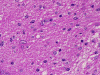

On low-magnification, cross section of the optic nerve gives a "double barrel" structure. The general outline of an optic nerve can still be appreciated (delimted by Þ in Panel A). There is a moderately cellular population of cells in between the dural sheath ( in Panel A) and the optic nerve. On medium-magnification, the vascular septa of the optic nerve is preserved (Panel B). On high-magnification, the optic nerve contains a mixture of cells with enlarged, mildly pleomorphic nuclei that are neoplastic astrocytes. Some cells with small nuclei are present and probably represent residual and reactive non-neoplastic astrocytes (Panel C and D). Cytoplasmic processes of some of tumor cells appear finely fibrillary (Panel C) while others are corase (Panel D). The cells in between the optic nerve and the dura is a mixture of irregular, hypercellular islands of neoplastic glial cells (delimted by Þ in Panel E) and hypocellular islands of slightly eosinophic, spindle cells. The later population represents reactive proliferation of meningothelial cells. The cytologic features are better appreciated in high-magnification (Panel F).

Microscopically, ONG in children are almost all pilocytic astrocytomas. The optic nerve is expanded. The fibrovascular septa within the optic nerve are separated by the tumor cells but the structure can still be well recognized as an optic nerve on cross section. Three major patterns are recognized 1. In the first pattern, the tumor is finely reticulated. In the second pattern, the tumor has microscysts and is coarsely reticulated. In the third pattern, the tumor cells are coarsely fibrillated, spindle shaped, and form bundles. There is minimal pleomorphism in the nuclei and it is not always easy to separate the neoplastic cells from adjacent reactive gliosis. There is a usually lack in mitotic activity, endothelial proliferation, and necrosis. Immunohistochemistry, the tumor cells are strongly reactive for glial fibrillary acidic protein (GFAP).

ONGs often extend into the subarachnoid space and inflict a prominent proliferation and thickening of perioptic meninges. This proliferation is composed of meningothelial cells, fibroblasts, and neoplastic astrocytes. Such changes are also known as arachnoidal hyperplasia or arachnoidal gliomatosis. The tumor tends to have coarsely fibrillated spindle cells may not be easily to be separated from the meningothelial cells and fibroblasts due to the intermingled architecture. Immunohistochemistry for GFAP is very helpful in separating the two components.